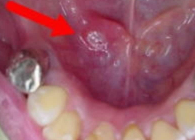

■ 구내염 사례 사진 2 조금 큰 구내염 사진.사례 사진.

조금 큰 애프터성 구내염 사진. 혀 밑에 있는 점막에 생겼음을 알 수 있다.

또한 왼쪽 구내염 사진처럼 딱딱한 물건이 전혀 접촉하지 않는 곳인 혀 밑 등에 생길 수도 있다. 심지어 혀의 측면 등에도 잘 할 수 있는 것들이 있다. 구내염은 입 안의 점막이라면 아무 곳도 선택하지 않는다.